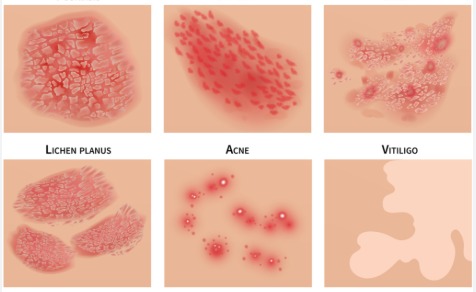

Skin Disorders

समस्त त्वचा रोग

Psoriasis/Eczema

सोरायसिस/ खुजली